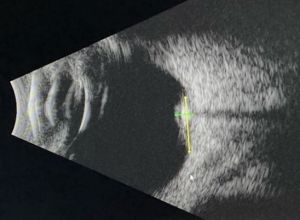

B Scan Ultrasonography

B scan can help assess tumor size and intralesional calcifications (Figure 3). Typical features are:

- High internal reflectivity

- Shadowing from intralesional calcifications

- Clear vitreous

- Typical dimensions: 6.0-6.25 mm base, 1.75-2.3 mm height[1][2][8]